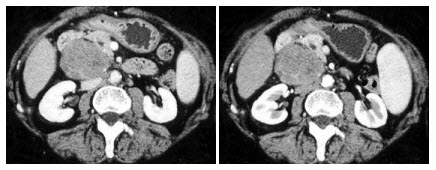

男,45岁,右腰部隐痛不适伴无痛性肉眼血尿1月,结合所示图像,最可能的诊断是()

A.右肾癌

B.右肾血管平滑肌脂肪瘤

C.右肾感染性囊肿

D.右肾盂癌

E.右肾脓肿

5、单项选择题 关于第六脑室的描述,不列哪项是错误的()

22、多项选择题

女,14岁,左腰部胀痛,CT平扫+增强如图所示,下列说法正确的是()

A.左肾实质内可见两个类圆形的囊性病灶,边缘光整,增强后不强化

B.左肾后外侧缘可见一较大的囊性病灶,其壁薄而光整,考虑为肾包膜下囊肿

C.左肾后外侧缘可见一较大的囊性病灶,其壁薄而光滑,考虑为肾外囊性病灶

D.考虑为多囊肾

E.考虑为多发性肾囊肿

23、单项选择题 心包上隐窝与气管前淋巴结的鉴别要点不包括()

34、多项选择题

女,64岁,左侧腰部胀痛,行CT扫描,如图所示,下列说法正确的是()

A.左肾区可见一巨大的占位性病灶,境界较清楚,胰腺尾部受压向前推移

B.该病灶密度不均匀,其内可见脂肪密度影,且呈不均匀强化

C.考虑为左肾来源的血管平滑肌脂肪瘤

D.考虑为左侧肾上腺来源的髓样脂肪瘤

E.考虑为腹膜后来源的脂肪肉瘤